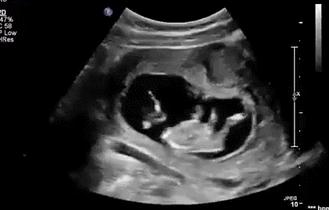

等到他再大点的时候,“蛙泳”项目已经无法进行了,但是你以为他长大点了就会听话、懂事,当个乖宝宝吗?

咦?这地儿怎么越来越小了,不管,我挤,我顶......

顶了这么久,“房子”怎么还是这么小?

管他呢,我要出去,我要游泳,我继续蹬腿,我蹬……